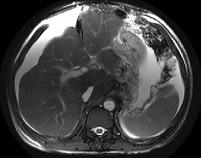

男,44岁,有乙肝病史,现腹胀,右上腹痛,消化不良,消瘦、乏力、贫血、黄疸,血清转氨酶升高,清蛋白/球蛋白比值倒置。CT、MRI检查如下图,最准确的诊断是...

问题 男,44岁,有乙肝病史,现腹胀,右上腹痛,消化不良,消瘦、乏力、贫血、黄疸,血清转氨酶升高,清蛋白/球蛋白比值倒置。CT、MRI检查如下图,最准确的诊断是 ( )

选项 A.肝硬化并腹水 B.肝硬化并腹水、再生结节 C.肝硬化腹水、肝癌 D.肝硬化并再生结节 E.肝硬化并腹水、脂肪肝

答案 B